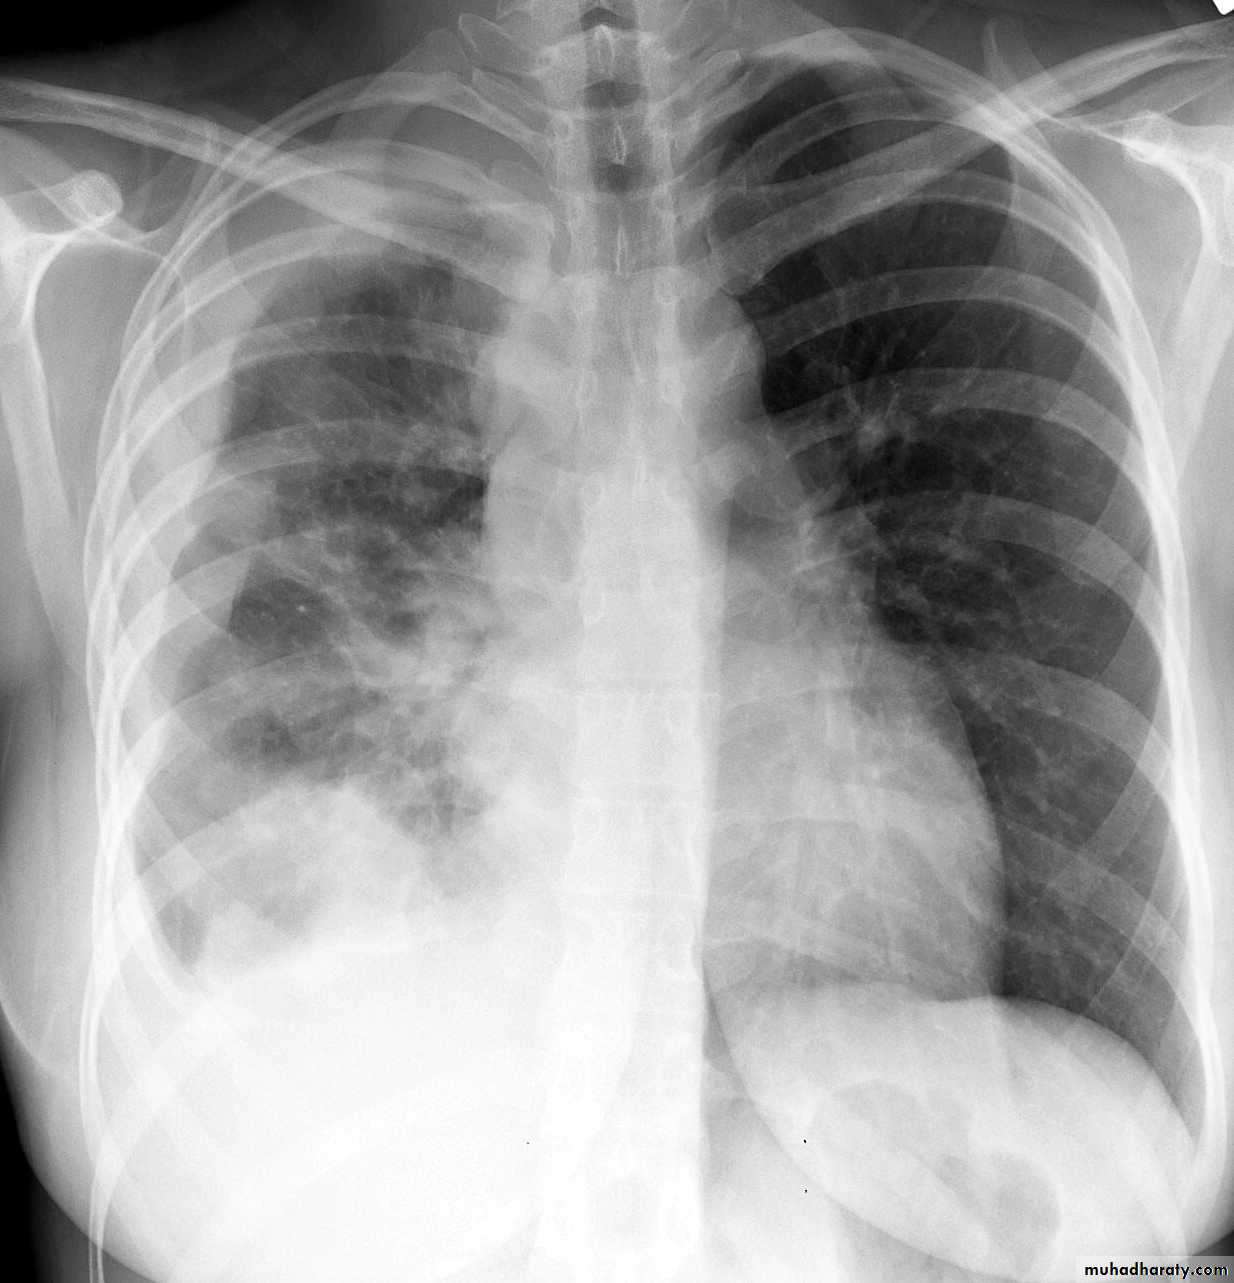

CXR:

Treatment